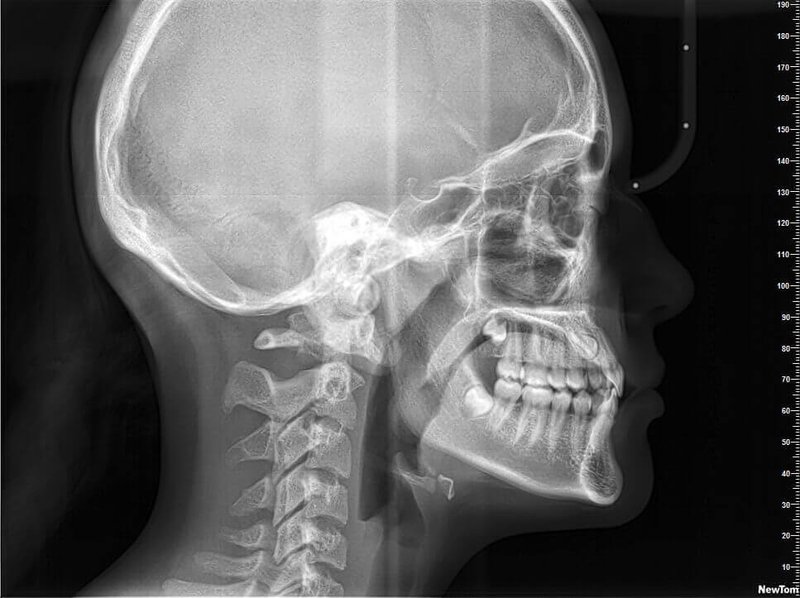

КОМПЛЕКСНЫЙ ГИБРИДНЫЙ КЛКТ ДЛЯ 2D/3D ВИЗУАЛИЗАЦИИ. ИЗОБРАЖЕНИЯ В ВЫСОКОМ РАЗРЕШЕНИИ С ЗАХВАТОМ МЕЛЬЧАЙШИХ ДЕТАЛЕЙ

GIANO HR – универсальное обновляемое устройство от NewTom для всех задач, связанных с радиографией. Благодаря полному диапазону опций 2D и 3D исследования для стоматологии оно предлагает множество особых трехмерных обследований для челюстно-лицевой хирургии, оториноларингологии и осмотра шейного отдела позвоночника. Визуализация только наивысшего качества с технологиями и опытом NewTom

NNT – программное обеспечение NewTom, предоставляющее несколько специальных режимов применения для имплантологии, эндодонтии, пародонтологии, челюстно-лицевой хирургии и радиографии. Это мощное технологически новейшее устройство, разработанное, чтобы снимать и обрабатывать изображения в несколько простых шагов для получения информации, необходимой для конкретного подробного диагноза пациенту. Продвинутое устройство, дающее врачу специальные инструменты для измерения анатомической области (расстояния и углы), нахождения нижнего альвеолярного нерва и замера объема верхних дыхательных путей.

NewTom GiANO HR новейшая модель была официально представлена на международном конгрессе радиологов ECR 2018 в марте в Вене. Благодаря обновленным системам механики и запатентованным механизмам работы аппарат отличается от своих сверстников Высочайшим качеством получаемых изображений, как 2D, так и 3D. Лучшее качество снимков и мы отвечаем за это! Этот аппарат заменит три аппарата! Панорамный аппарат, цефалометрическая приставка и конусно-лучевая компьютерная томография интегрированы в единую платформу. В комплекте детектор для выполнения 3D исследований с захватом области 13х16 см, Сьемный 2D CMOS детектор для выполнения панорамных исследований, и ТРГ.